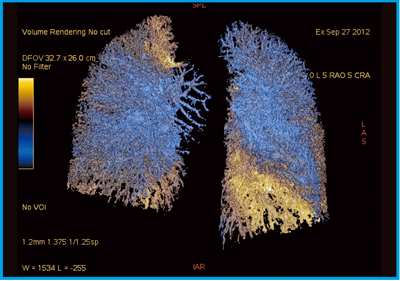

N-NOSEの最新研究論文発表会」N-NOSEが再発モニタリングツール, 分子イメージング(核医学) - Siemens Healthineers Japan,

分子イメージング(核医学) - Siemens Healthineers Japan, 津野田 雅敏 | 放射線科 | 診療科・部門 | 心臓病センター榊原病院,